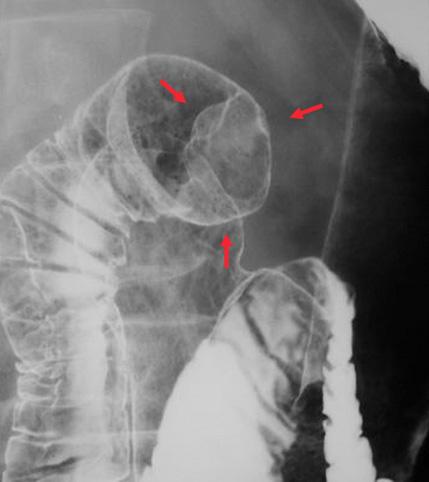

疾患(病理主体)の分類カルチノイド腫瘍/

部位(臓器別)十二指腸/球部

検査方法X-P

腫瘍の肉眼分類1型(腫瘤型)/

病変の最大径(ミリ)10〜14